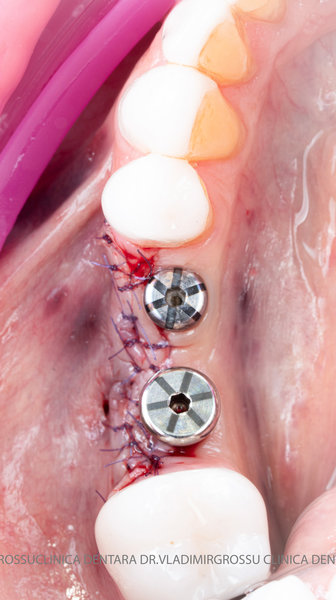

Aditia gingivală este o procedură chirurgicală ce corectează diverse probleme estetice și funcționale, cum ar fi recesiunea gingivală. În implantologia modernă, aditia de țesut moale este utilizată aproape în fiecare intervenție de inserție a implantului dentar pentru a asigura un aspect estetic natural și o bună integrare a implantului în cavitatea bucală.

Adiția osoasă are un rol crucial pentru poziționarea corectă și stabilă a implanturilor dentare. Clinica stomatologică Dr. Grossu din Chișinău promovează o abordare chirurgicală estetică și predictibilă, adaptată fiecărui caz în parte.